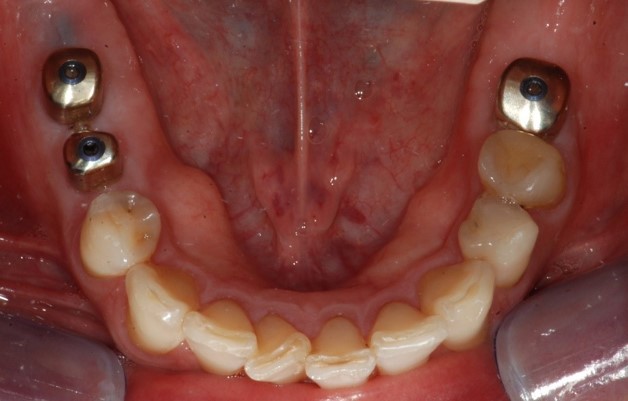

Fig. 1. Foto che mostra l’edentulia dei settori posteriori mandibolari.

Il paziente, in buono stato di salute generale, si presentava con un’edentulia dei settori posteriori dell’arcata mandibolare. In particolar modo, all’esame obiettivo, si evidenziava l’assenza di tutti i molari inferiori e del secondo premolare di destra (Figure 1,2). Il paziente riferiva la perdita degli elementi dentali da qualche anno per motivi di carie e fratture, inoltre diceva di non aver mai provveduto ad una nuova riabilitazione principalmente per mancanza di tempo, a causa dei tanti impegni di lavoro. Si pianificava quindi una riabilitazione implantare degli elementi 45-46 e 36, da eseguire in chirurgia guidata in un’unica seduta, e con l’inserimento di nuovo tipo di abutment di guarigione chiamato Profile Designer iPhysio® (Lyra ETK, Sallanches, Francia) in grado di ridurre i tempi legati alle fasi di protesizzazione degli impianti.